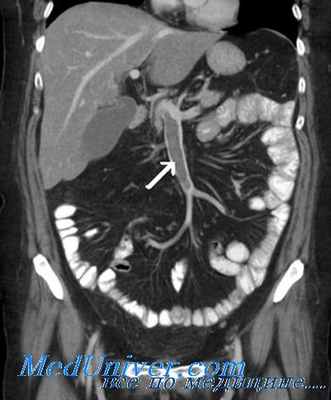

Ангиография при мезентриальном тромбозе

Методом выбора в диагностике нарушения мезентериального венозного кровообращения считается компьютерная томография с контрастированием. Общая диагностическая точность составляет 95—100% [18]. Этот метод не только позволяет определить степень окклюзии, уровень тромбоза и его распространенность, но и предоставляет важную информацию, касающуюся жизнеспособности кишечника, что имеет огромное значение в плане выбора лечебной стратегии. Выявление таких признаков, как наличие расширенных петель кишечника, утолщение их стенок, содержание пузырьков газа в стенке кишки или в венозной системе, говорит об ишемическом повреждении кишки и диктует необходимость выполнения экстренной операции. Высокая чувствительность и специфичность метода (90 и 92% соответственно) в выявлении ишемии кишки определяют его использование в качестве метода выбора и как можно раньше у больных с подозрением на наличие этого коварного состояния [19, 20].

Другие методы исследования, такие как мезентериальная ангиография, ядерная сцинтиангиография, из-за инвазивности, а также необходимости специального оснащения в диагностике тромбоза венозной мезентериальной системы используются редко [5, 17].